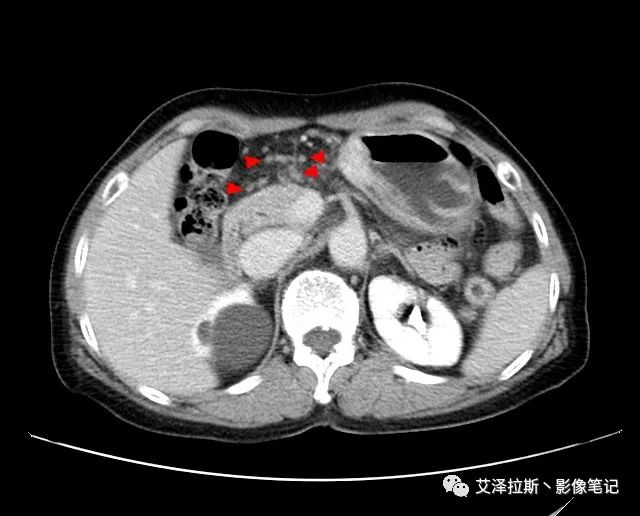

【基本情況】 患者,女性,66歲,貧血。

【影像所見】 胃竇部狹窄,胃壁環形增厚,小彎側見一巨大潰瘍,周圍伴“環堤征”,漿膜面不完整,胃周脂肪見網格狀條索影,病灶與肝臟左葉、胰腺鉤突脂肪間隙消失,增強掃描病灶明顯強化。引流區內約15個區域淋巴結受累。